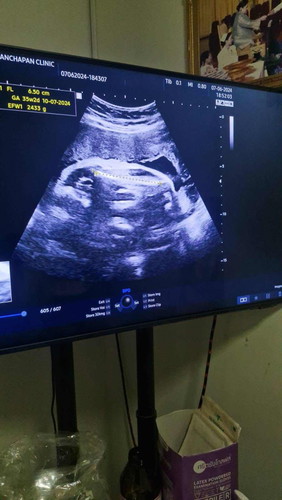

33+4 วีค น้องน้ำหนัก 2,433 แบบนี้มาตรฐานหรือเยอะไปหรือเปล่าคะ

กำหนดคลอดน้อง 22 กรกฏาคม น้องจะน้ำหนักเยอะมากไหมคะ พอดีอยากคลอดธรรมชาติแต่กลัวน้องจะตัวใหญ่เกินแล้วต้องผ่าคลอดค่ะ #ขอความคิดเห็นของคุณแม่หน่อยค่ะ #ท้องแรก